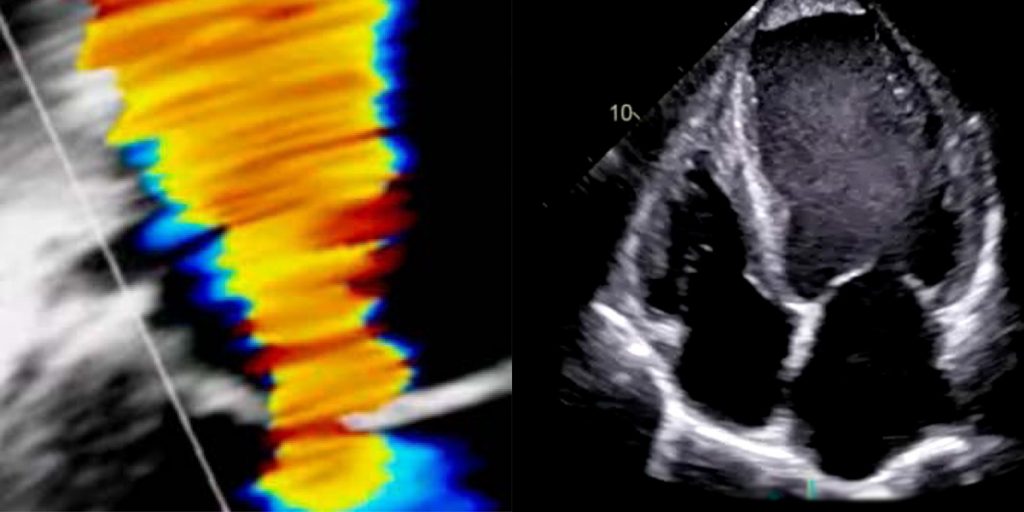

DEGUM Grund- & Aufbaukurs Echokardiografie

Die DEGUM Kurse Echokardiografie vermitteln ein strukturiertes und praxisnahes Verständnis der kardialen Ultraschalldiagnostik. Von den physikalischen Grundlagen bis zur differenzierten Beurteilung komplexer Befunde werden alle relevanten Aspekte der modernen Echokardiografie systematisch vermittelt.

Die Echokardiografie ist eines der wichtigsten bildgebenden Verfahren in der Kardiologie und spielt eine zentrale Rolle in der Diagnostik, Risikostratifikation und Therapiekontrolle kardiovaskulärer Erkrankungen. Ihre breite Verfügbarkeit, die fehlende Strahlenbelastung und die unmittelbare klinische Anwendbarkeit machen sie zu einem unverzichtbaren Instrument im ambulanten und stationären Alltag. Die DEGUM Kurse Echokardiografie vermitteln ein umfassendes Verständnis dieser Methode – von den Grundlagen bis zur spezialisierten Anwendung.

Im Grundkurs steht die systematische Herangehensweise an die echokardiografische Untersuchung im Vordergrund. Dazu zählen die physikalischen Grundlagen der Ultraschalldiagnostik, die standardisierte Bildakquisition sowie die strukturierte Befundung. Die korrekte Darstellung kardialer Anatomie, die Beurteilung der links- und rechtsventrikulären Funktion sowie die Identifikation typischer Herzklappenerkrankungen bilden die Basis für eine zuverlässige Diagnostik. Ergänzt wird dies durch praktische Übungen und Live-Demonstrationen, die eine direkte Umsetzung des theoretischen Wissens ermöglichen.

Der Aufbaukurs erweitert diese Grundlagen um komplexe klinische Fragestellungen und moderne echokardiografische Techniken. Dazu gehört insbesondere die differenzierte Analyse von Herzklappenerkrankungen, die Beurteilung von Klappenprothesen sowie die Einschätzung hämodynamischer Zusammenhänge. Darüber hinaus werden fortgeschrittene Verfahren wie 3D-Echokardiografie, Speckle-Tracking und Kontrastechokardiografie vermittelt, die eine präzisere Charakterisierung kardialer Strukturen und Funktionen ermöglichen.